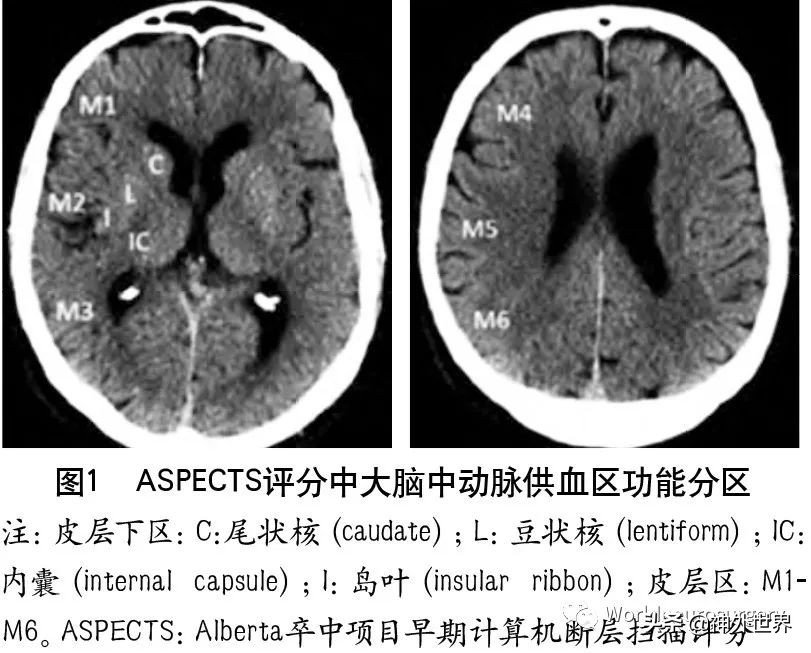

3.2.1 ASPECTS评分

ASPECTS评分是基于NCCT评估MCA区域早期缺血改变简单而系统的一种方法。将MCA供血区各主要功能区分别赋分(4个皮层下区:尾状核C、豆状核L、内囊IC、岛叶I;6个皮层区,标志为M1-M6)(图1),共计10分,每累及一个区域减去1分,即正常脑CT为10分,MCA供血区广泛梗死则为0分。

为评估后循环梗死患者早期梗死情况,PUETZ等 建立了评估后循环的AIS预后早期CT评分(posterior circulation Acute Stroke Prognosis Early CT score,pcASPECTS)。pc-ASPECTS总分也是10分:双侧丘脑和小脑各1分,双侧大脑后动脉供血区各1分,中脑和脑桥为2分(图2)。